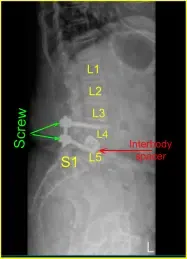

A patient who had previously undergone a L4/5 lateral interbody fusion, but ended up developing severe left leg radiculopathy and then moderate right leg radiculopathy, associated with severe piriformis syndrome.

Given the concern for the implant in the prone position and our feeling that the endplates may have fractured more, we exposed the transverse processes for L4 and L5 and used the drill to create pilot holes in the pedicle on the left side at L4 and L5. Under fluoroscopy, we guided probes through the pedicles and tapped each pedicle, then placed pedicle screws into L4 and L5.

These screws were stimulated, and checked under fluoroscopy, and then a rode was placed and cap screws were given a final tightened. On the right side and left side, we decorticated the facets and transverse processes and placed our fusion mass for arthrodesis.